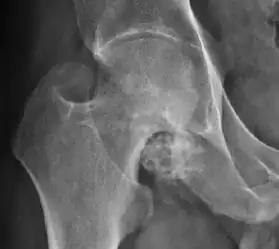

Plain radiography allows us to categorize the hip as normal or dysplastic or with impingement signs (pincer, cam, or a combination of both). Besides these, pathologic processes like osteoarthritis, inflammatory diseases, infection, or tumors can also be identified (Figure 1).[1]

Figure 1.

-

Radiography in normal hip -

X-ray in pincer impingement type of hip dysplasia -

X-ray of cam -

Hip in osteoarthritis -

Septic arthritis

X-ray in pediatrics

In adults, one of the main indications for radiographs is the detection of osteoarthritic changes (Figure 1(e)). Nevertheless, radiographs usually detect advanced osteoarthritis that can be graded according to the Tönnis classifications. The grading system ranges from 0 to 3, where 0 shows no sign of osteoarthritis. Intermediate grade 1 shows mild sclerosis of the head and acetabulum, slight joint space narrowing, and marginal osteophyte lipping. Grade 2 presents with small cysts in the femoral head or acetabulum, moderate joint space narrowing, and moderate loss of sphericity of the femoral head. Grade 3 is the severest form of osteoarthritis, which manifests as severe narrowing of the joint space, large subchondral cyst with productive bone changes that may lead to deformity of the bone components of the joint, while secondary osteoarthritis due to calcium pyrophosphate deposition can be diagnosed when calcification of hyaline cartilage and fibrocartilage is detected.[1]

There are other pathological conditions that can affect the hip joint and radiographs help to make the appropriate diagnosis. Acute bacterial septic arthritis can be diagnosed by radiographs when a fast regional osteoporosis and destructive monoarticular process develops (Figure 1(f)). In case of tuberculous or brucella arthritis it is manifested as a slow progressive process, and diagnosis may be delayed.[1]

Synovial chondromatosis can be confidently diagnosed by X-ray when calcified cartilaginous chondromas are seen. However, other synovial proliferative processes, such as pigmented villonodular synovitis, require MRI for accurate diagnosis, although noncalcified synovitis can be suspected in radiographs by indirect signs, such as soft tissue swelling and/or erosions in the femoral head, femoral neck, or acetabulum (Figure 7).[1]